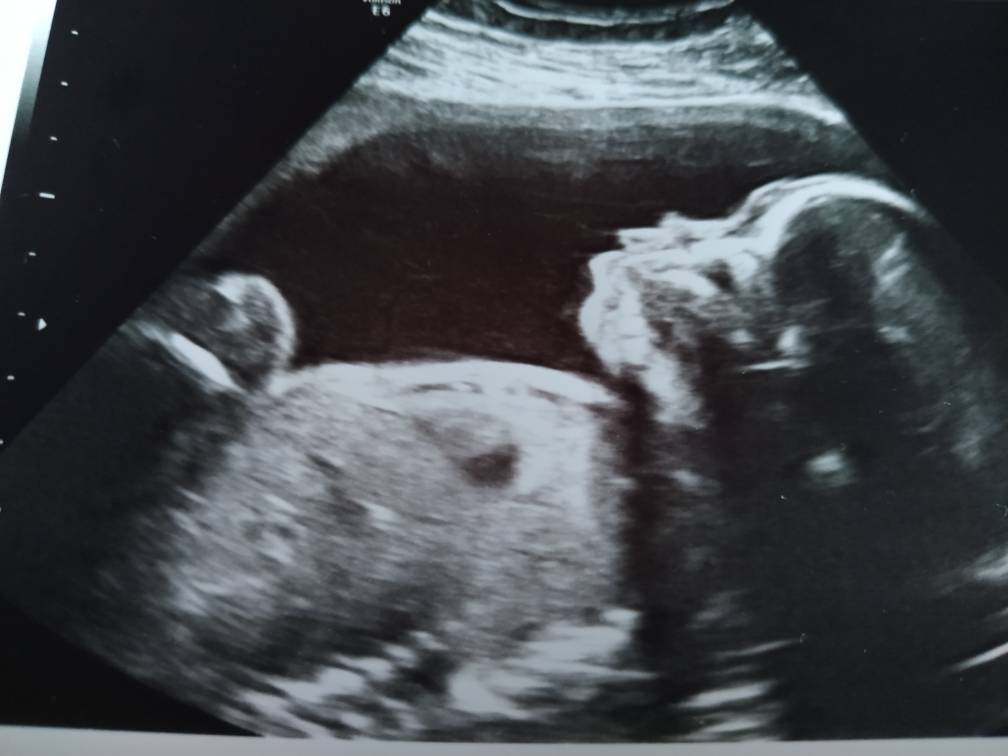

Bylam dzisiaj na USG a to moja kochana córeczka [emoji3590] Anastazja [emoji7][emoji7]Zobacz załącznik 996712